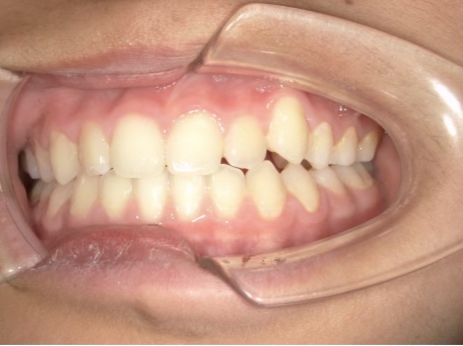

治療前① 小1:6y8m 初診

| カウンセリング・診断結果 | 前歯の生え変わり時期に来院されました。(写真①) 乳歯列期に受け口の既往があり切端咬合になりそうなため、受け口に対する矯正治療の考え方と対処法、当院のコンセプトを説明したところ治療を希望されたので診断を行いました。 診断の結果、上顎骨に対し下顎骨が長く、骨格的な構造も下顎突出型反対咬合(下顎骨が適切な位置よりも前に出ているタイプの受け口)と分かりました。 顔立ちは、中顔面が引っ込んだように見えるコンケーブに移行中です。 機能的な問題として低位舌があるため受け口の悪化が考えられることも説明し、以下の治療を提案しました。 |